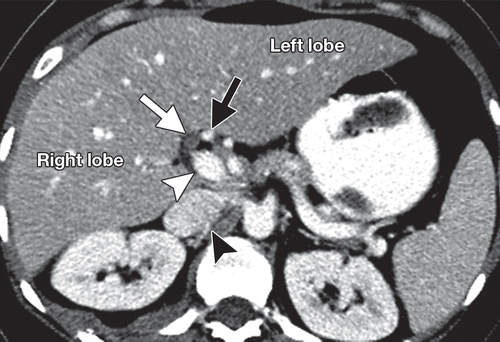

肝门,一般指第一肝门(first porta of liver),是肝脏的腹膜内中央裂隙(在内脏表面),分隔尾状叶(caudate lobe)和方叶(quadrate lobe),是门静脉(portal vein)、肝动脉(hepatic arterie)、肝管(hepatic duct)、肝神经丛和淋巴管等重要结构的出入口。

通过第一肝门,门静脉左、右支和肝固有动脉左、右支的血液流进肝脏;肝内左、右胆管排出胆汁到肝外胆管;肝左、中、右静脉出肝后汇入下腔静脉。

Glisson系统即肝门静脉、肝动脉、胆管在肝内的分、属支被结缔组织纤维鞘包绕而形成的三联管道系统,似树枝状分布于肝内。

肝静脉,Hepatic Vein,下腔静脉(Inferior vena cava,IVC)在肝内的左、中、右3支肝静脉,其走行区所形成的纵形切面(称为肝静脉裂)将肝分隔成4个部分。

正中裂,下腔静脉左前缘与其右前方的肝中静脉长轴的连线。将肝分为左、右半肝,裂中有肝中静脉走行

左叶间裂,镰状韧带左侧1cm处至下腔静脉左侧的连线,将左半肝为左内叶与左外叶,裂中有肝左静脉走行